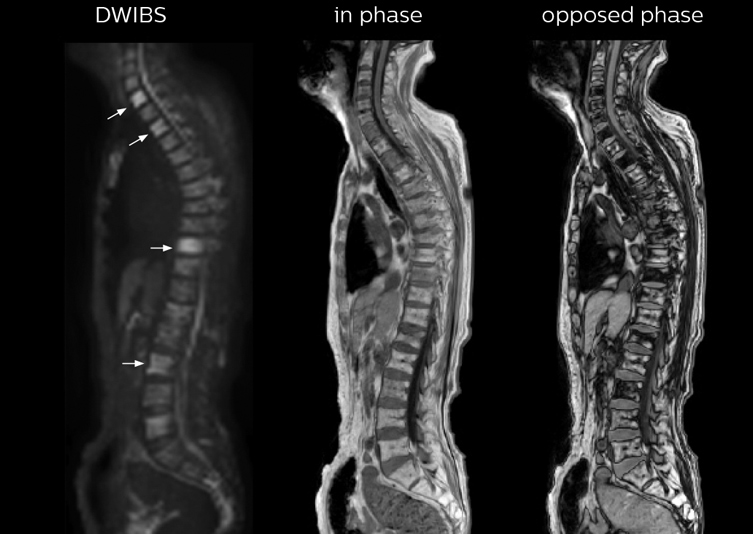

“In-phase and out-phase sagittal T1-weighted FFE images help us to visualize and further characterize bone lesions such as metastasis and bone-marrow hyperplasia that have high signal on DWI. These images are also used throughout radiotherapy, to monitor changes in the fatty bone marrow.”

The single shot T2-weighted TSE images are used for morphology and compared to DWIBS images to identify T2 shine-through. Sagittal STIR images are used in patients with inflammation or bone metastasis.